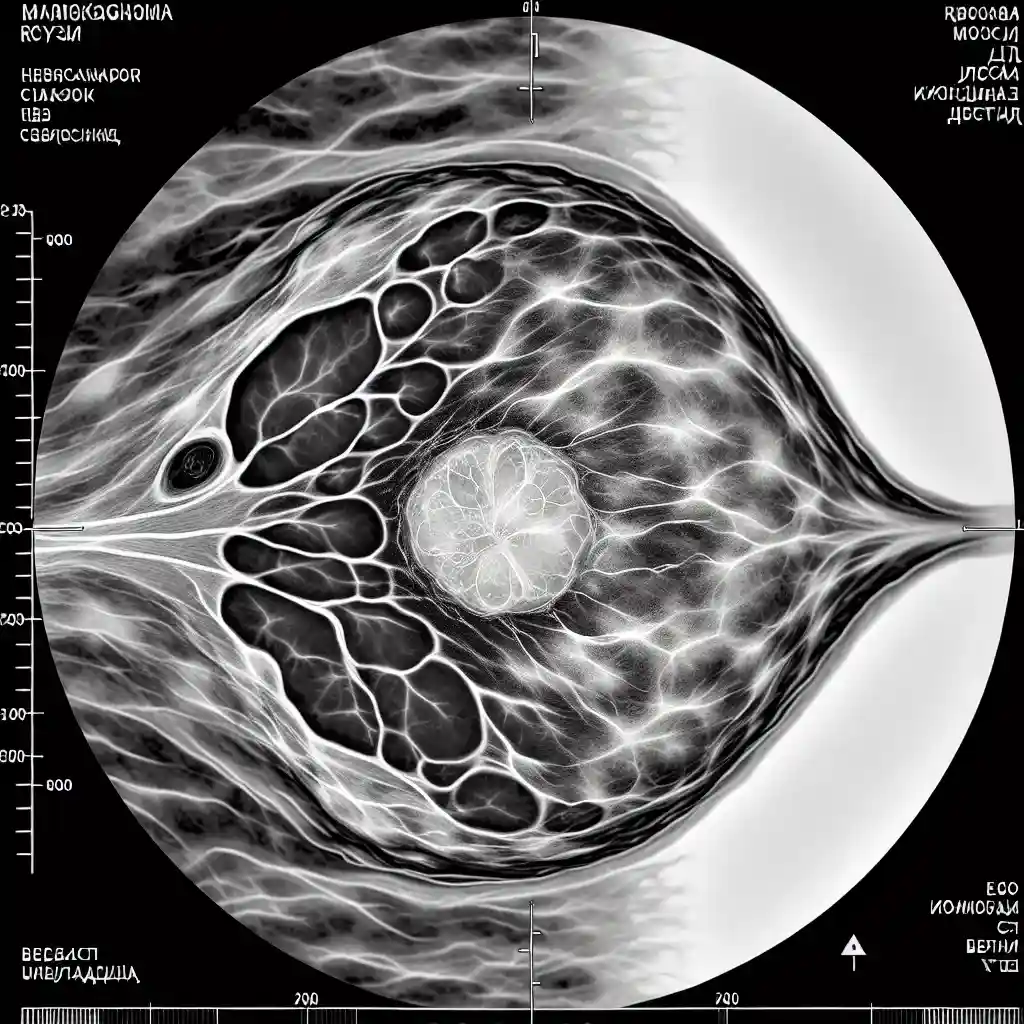

Фиброаденома на маммографии

Фиброаденома – одно из самых распространённых доброкачественных образований молочной железы, которое часто выявляют при маммографии. Благодаря современным методам диагностики, таким как маммография, врачи могут своевременно определить наличие фиброаденомы и дифференцировать её от других образований. В этом материале подробно рассмотрим, что такое фиброаденома на маммографии, как она выглядит, её признаки, а также методы диагностики и рекомендации по лечению. Если вы заботитесь о своём здоровье груди, эта информация будет крайне полезной.